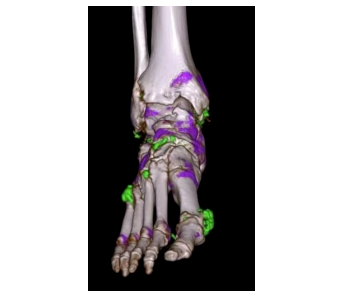

雙能量成像精準(zhǔn)識別病灶成分,可無創(chuàng)檢查痛風(fēng)

通過高低雙能量掃描,可區(qū)分鈣化、尿酸結(jié)晶、脂肪等成分,精準(zhǔn)定位痛風(fēng)石、腎結(jié)石成分,輔助制定個性化治療方案。 腫瘤活性分析、心肌缺血評估等功能,為腫瘤治療隨訪及心血管疾病診療提供分子級信息。